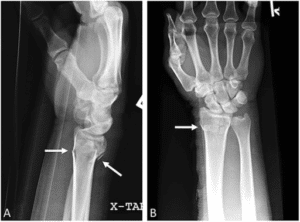

Colles – extraarticular with dorsal displacement and dorsal angulation, typically from fall onto extended wrist (Dinner Fork deformity).

Smith – extraarticular with volar displacement and volar angulation, typically from fall onto flexed wrist (Garden Spade deformity).

Barton – involves dorsal or volar intraarticular surface, often with radiocarpal dislocation/subluxation.

Chauffeur (aka Hutchinson fracture) – intraarticular fracture of the radial styloid process.